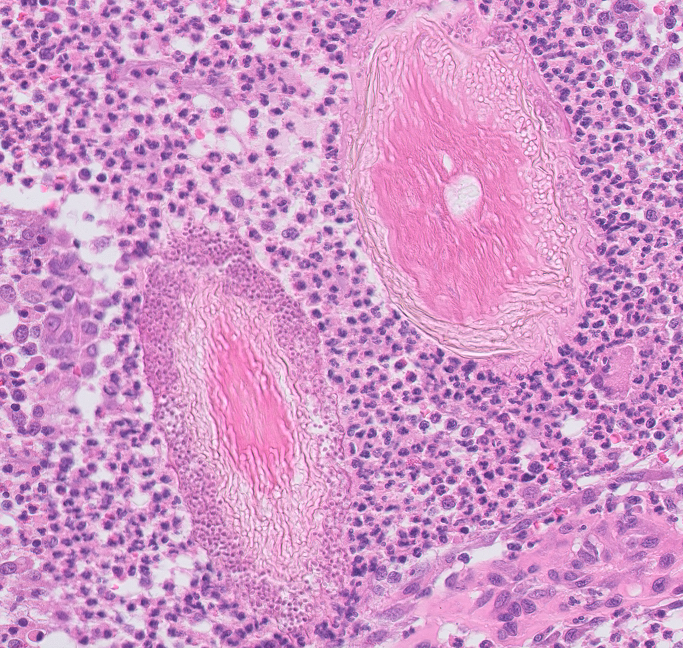

Canine: fibroadnexal hamartoma (also known as fibroadnexal dysplasia).

Canine: ringworm.